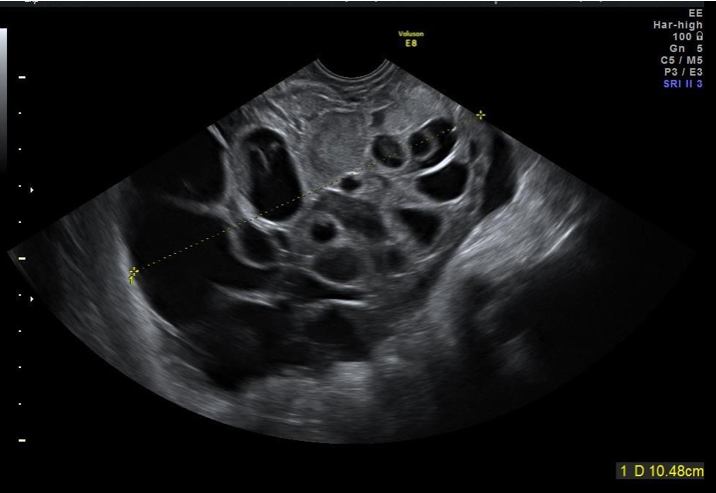

Gulesäckstumör är en ovanlig och högmalign tumör, som ofta uppträder hos unga kvinnor (vanligen 10–30 år). Stora studier saknas som beskriver ultraljudsmorfologin eftersom tumören är ovanlig, men enligt fallbeskrivningar är tumören oftast unilateral, stor (10–20 cm), solid och välvaskulariserad. Nekros kan förkomma. Se bild 4.

Bild 4. Gulesäckstumör, ”Yolksac tumor/endodermal sinus tumor”, hos 25-årig patient som sökt vård pga. blödningsrubbningar, förhöjt AFP.